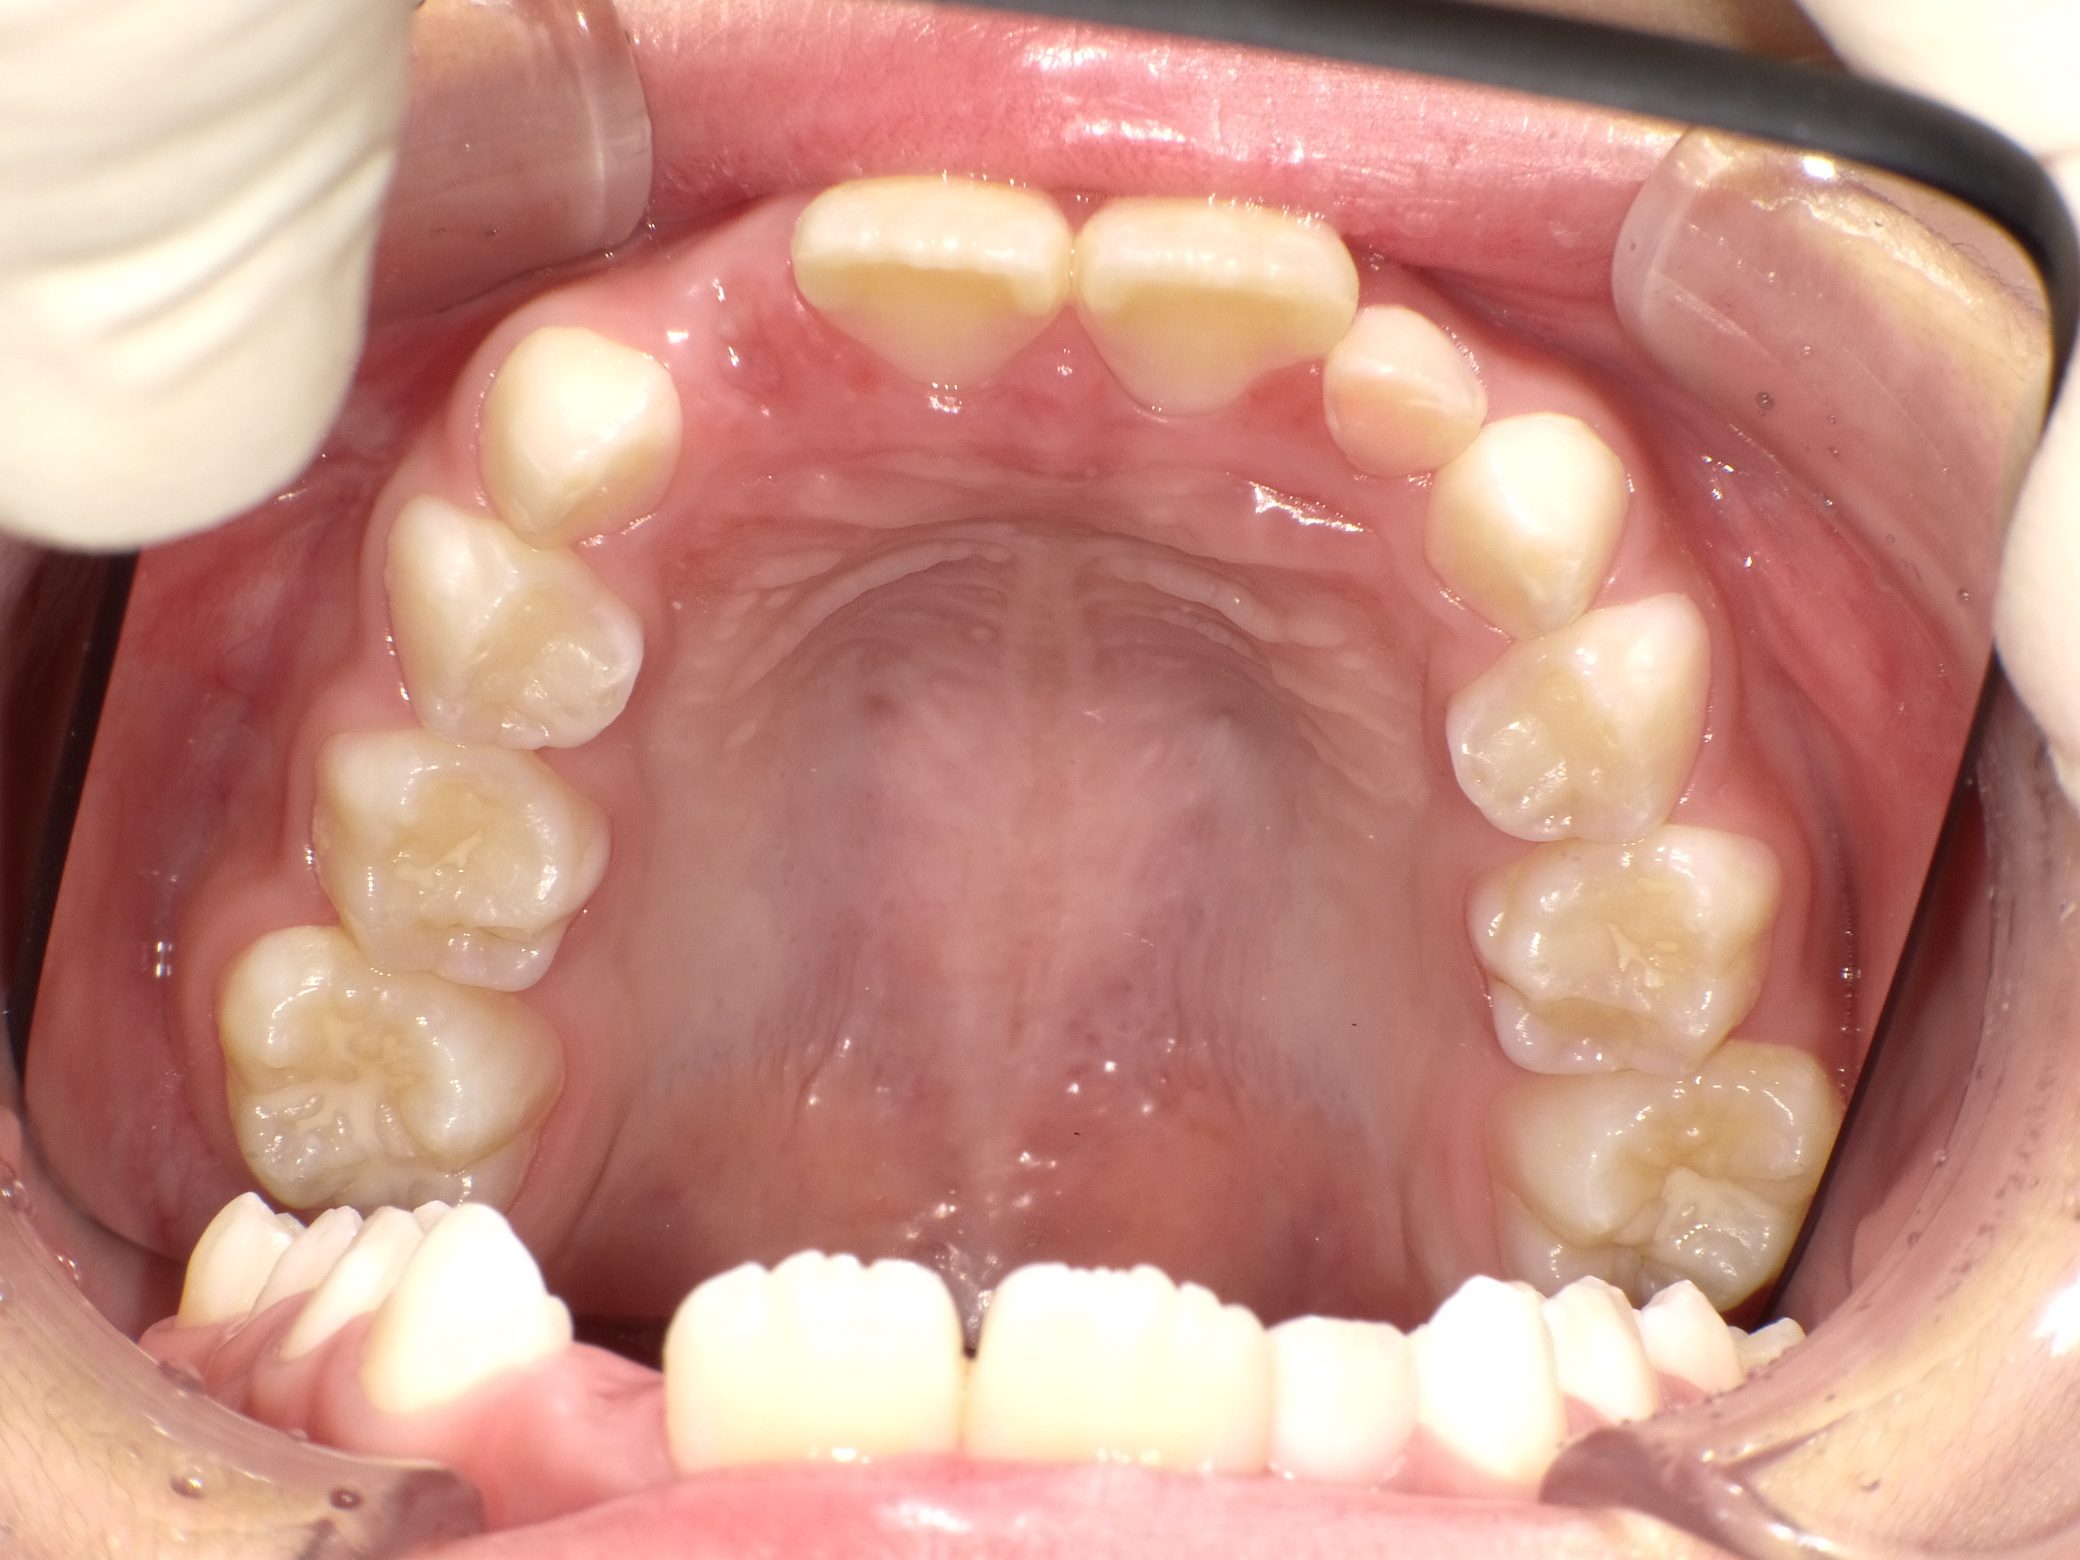

Before

After

【小学生】マイオブレース矯正 上顎前突(出っ歯)と叢生(でこぼこ)を改善

治療期間

2年

治療開始

8歳

種類

マイオブレース矯正

使用装置

機能矯正装置 咬合斜面版

現在は終了後8年たっていますが、今も定期健診にきてくれて 歯並びを保っています